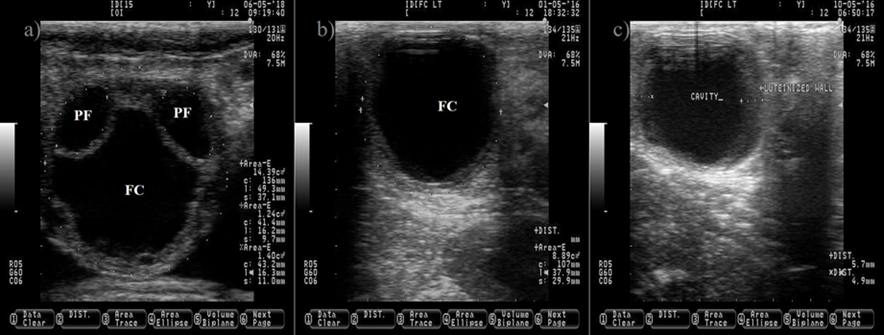

The anechogenic follicular fluid in the PF and FC makes them appear as a dark circle. Pictures b and c depict a FC after induced luteinization by GnRH injection, notice the increment on the thickness of the follicular wall (c). Pictures were taken using a 7.5 MHz probe.

Figure 3 Ovarian cyst in dairy cattle. a) picture depicting two normal pre-ovulatory (PF) follicles and one large follicular cyst (FC)

The causes of anovulatory condition include a low LH pulse frequency after estrus23 and the formation of follicle cyst (Figure 3). A follicle cyst is a large follicle that fails to ovulate and persist for an abnormal period of time in the absence of a CL, causing a recurrent estrus behavior. A sub-luteal progesterone concentration24 that allows a rise of LH pulse frequency to sustain follicle growth25, but not a preovulatory LH surge to induce ovulation26, favors follicle cyst formation. In addition, the induction of a preovulatory LH surge without subsequent progesterone exposure is also effective to induce follicle cyst formation27.

The follicle cyst appears as a large ovarian structure (> 25 mm in diameter) with a thin wall (< 3 mm), a non-echogenic antrum, a large estradiol: progesterone ratio and it can rupture if mishandled during palpation (Figure 3). Another type of cyst is the follicle-luteal, also known as luteinized follicle or luteinized cyst. The luteinized follicle cyst has a thick wall (> 3 mm), a reduced cavity, a small estradiol: progesterone ratio and it will not rupture during palpation (Figure 3)28,29. A luteinized follicle cyst might appear after treatment of follicle cyst with GnRH injections. Ovulation and release of the oocyte from the preovulatory follicle are paramount events that open the possibility for pregnancy. After these events, the next expected ovarian structure to develop is the CL.